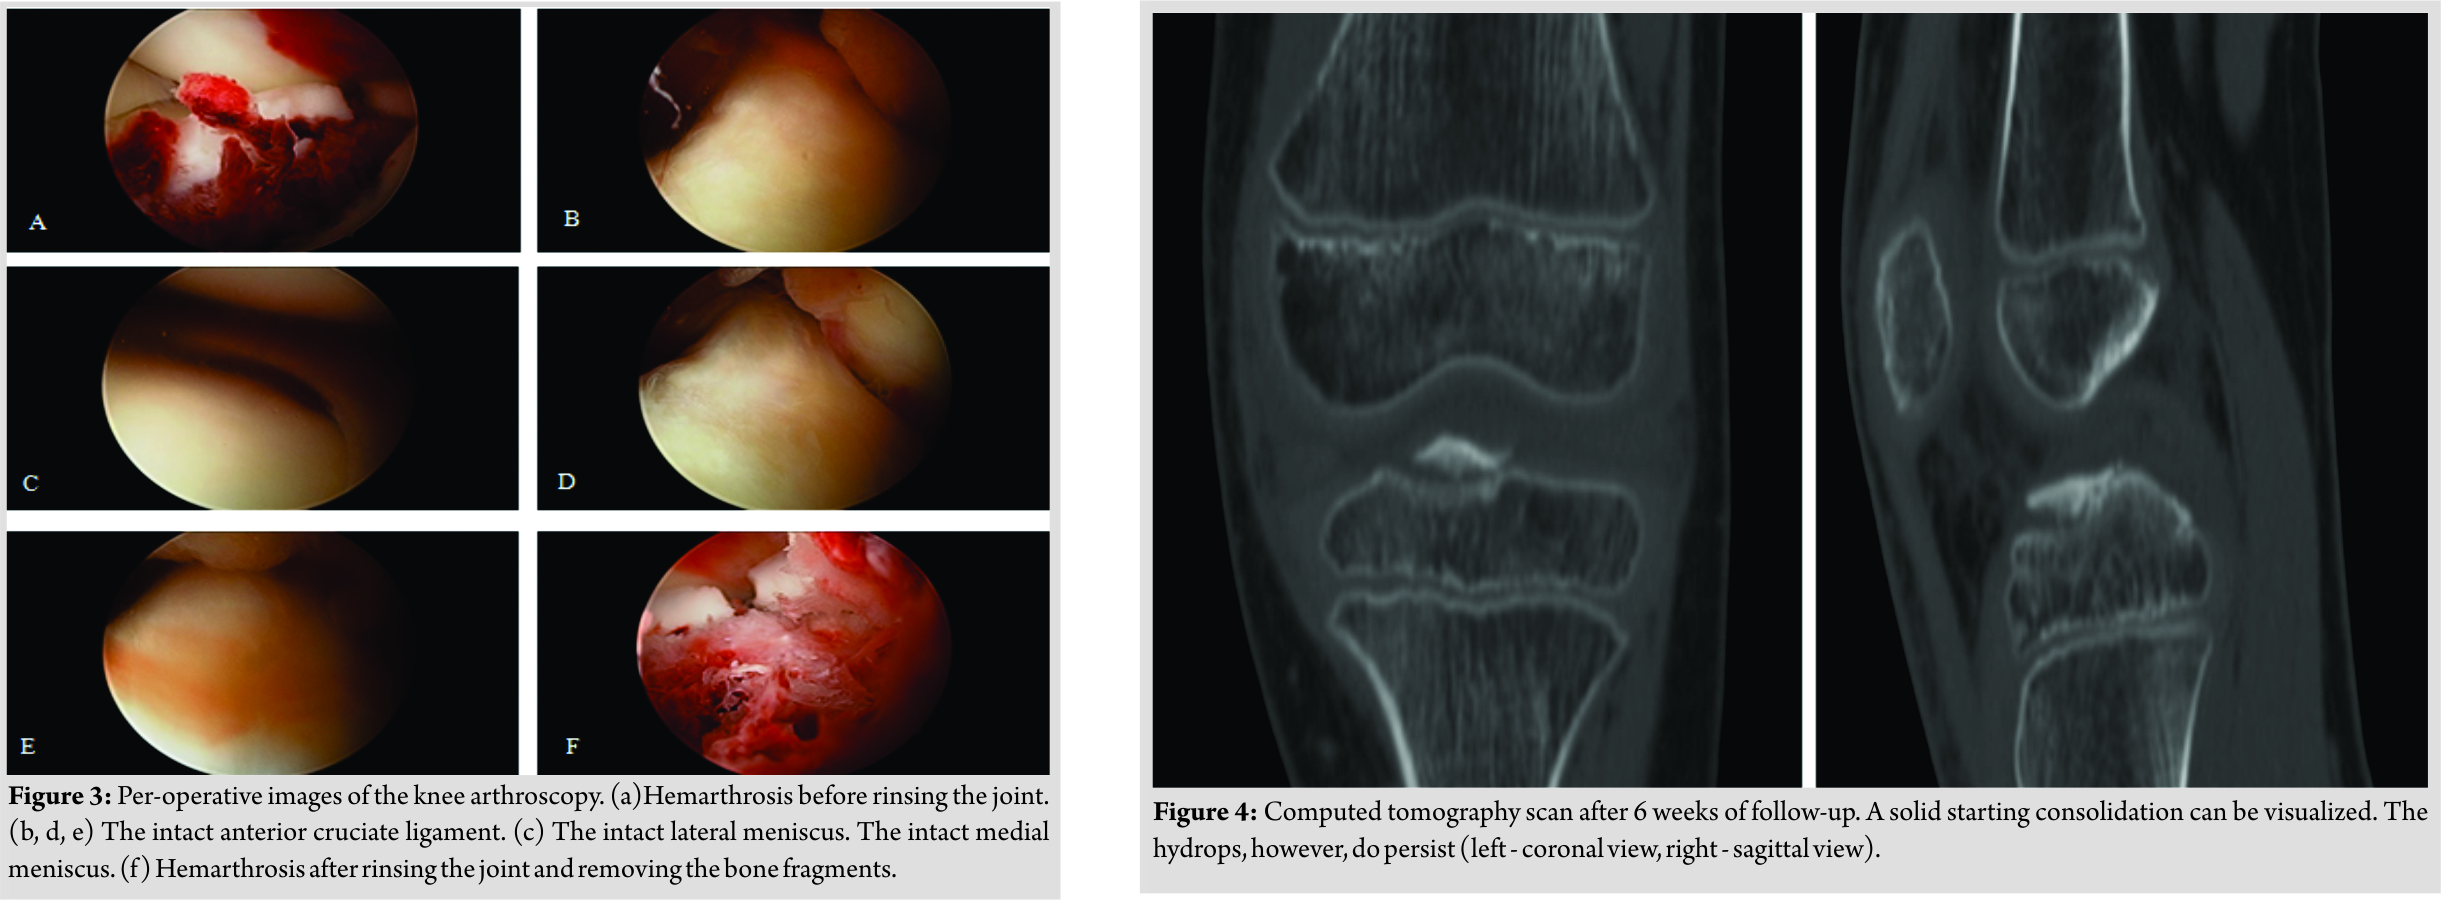

A male Caucasian 8-year-old child presented at the hospital’s emergency department in Belgium. The circumstances of the accident were reported as a fall on the left knee complicated by a contact trauma with another child. At consultation presenting, complaints were a sharp pain in his left knee and difficulties to walk. The pain was scored as 4/10 on the visual analogue scale. In clinical examination, anterior pressure pain, swelling, and a restricted range of motion(flexion up to 100° and extension deficit of 5°) were the main findings. Performing ananterior drawer test and Lachman test, no laxity was documented. On conventional anteroposterior and lateral view of the X-ray, a minimal displaced fracture of the intercondylar eminence, two loose bone fragments, and a bloated suprapatellar bursa indicating hemarthrosis could be evidenced (Fig. 1). A CT scan confirmed a fracture of the intercondylareminence (Fig. 2). The fracture was classified as Meyers and McKeever Type II [4]. The initial treatment provided an adequate pain management with appropriate analgesics and plaster immobilization in 0–5° of flexion. Based on the clinical and radiological findings, a knee arthroscopy was performed 3daysafter injury. The indication for arthroscopic surgery was removal of the intra-articular bony fragments and to evaluate whether the fracture was stable. The fracture of the proximal tibia was visualized through arthroscopy (Fig. 3).

The ACL was still intact yet showed a discrete laxity. No other fractures or injuries were visualized. Furthermore, the joint was rinsed and the loose bone fragments were removed to improve thee xtension and deep flexion. Peroperatively, the ROM was tested and was complete. Postoperatively, the knee was immobilized in extension with a hard cast. Weight-bearing was not allowed. Physiotherapy was established to strengthen and stabilize the knee. In the first follow-upconsultation 1 week after surgery, a new hard cast was applied for one more week. The patient was instructed to continue the isometric exercises for adequate revalidation. After 2 weeks of cast immobilization, an extension brace was applied for another 2–3 weeks. 6 weeks after the initial trauma, clinical examination showed a positive clinical course. A follow-up CT scan was performed (Fig. 4) that could show a starting consolidation. A CT scan examination was discussed with the family of our patient since his wish was to start sporting (football) early. Furthermore, CT scan is superior to X-ray with the disadvantage of a higher radiation dose. The extension brace was removed and a soft walking brace was applied. The patient was allowed to walk by full weight-bearing, taking pain and stability into account. A T1-weighted magnetic resonance imaging (MRI) scan was performed at 8weeks of follow-up (Fig. 5).This examination was initially performed because of a new trauma and was ordered by the general practitioner. However, it is useful to present the result of the MRI in this case report. The MRI showed an almost complete consolidation alongside very limited edema of the bone (Fig. 5a and b). The ACL and posterior cruciate ligament (PCL)weretotally intact (Fig. 5c and d). Clinically, the knee showed normal stability. The walking brace was permanently removed, and the patient was allowed to perform routine daily activities including all sportive activities. No more follow-up consultations were planned.